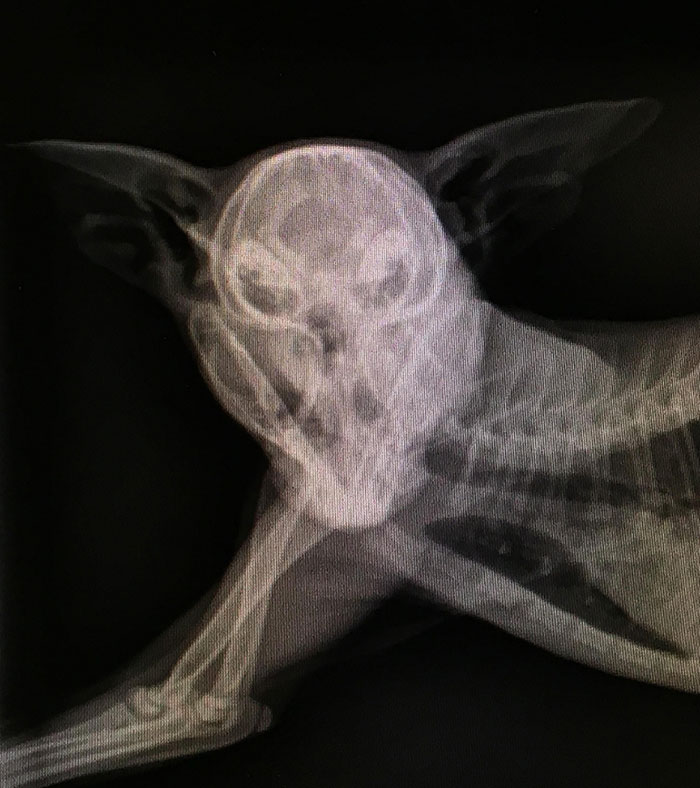

X-Ray Of A Pregnant Dog